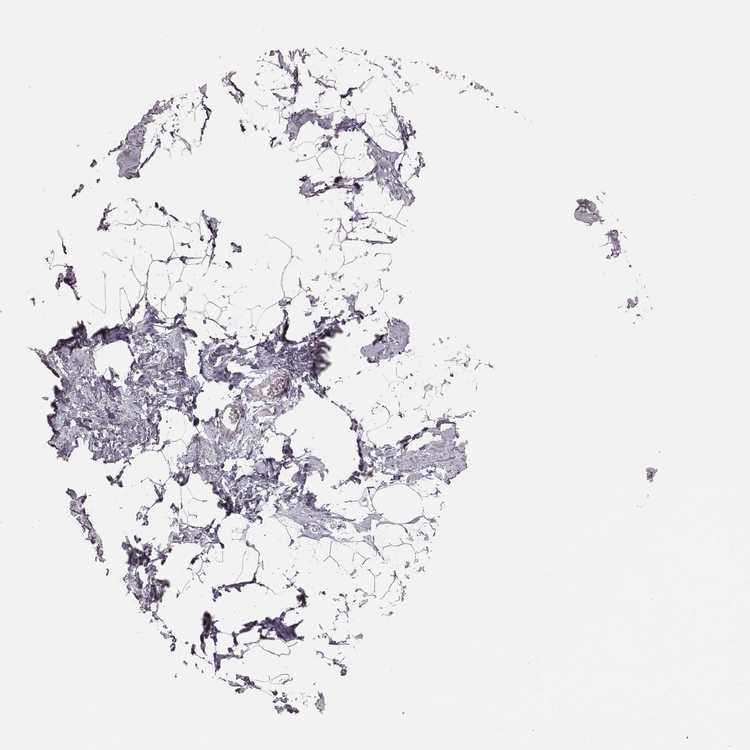

BREAST - Antibody stainingi

Antibody staining in the annotated cell types in the current human tissue is reported as not detected, low, medium, or high, based on conventional immunohistochemistry profiling in selected tissues. This score is based on the combination of the staining intensity and fraction of stained cells.

Each image is clickable and will lead to virtual microscopy that enables deeper exploration of all samples and also displays staining intensity scores, fraction scores and subcellular localization as well as patient and tissue information for each sample.

Antibody HPA070395

Adipocytes Not detected

Glandular cells Not detected

Myoepithelial cells Not detected